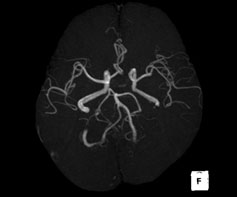

脳梗塞、脳腫瘍、脳出血などの頭蓋内病変を診断するための検査です。 また、造影剤を用いること無く血管を明瞭に描出することができるので、動脈瘤や血管狭窄などの診断に有用です。

頭部MRI検査の画像 頭部MRI検査の画像